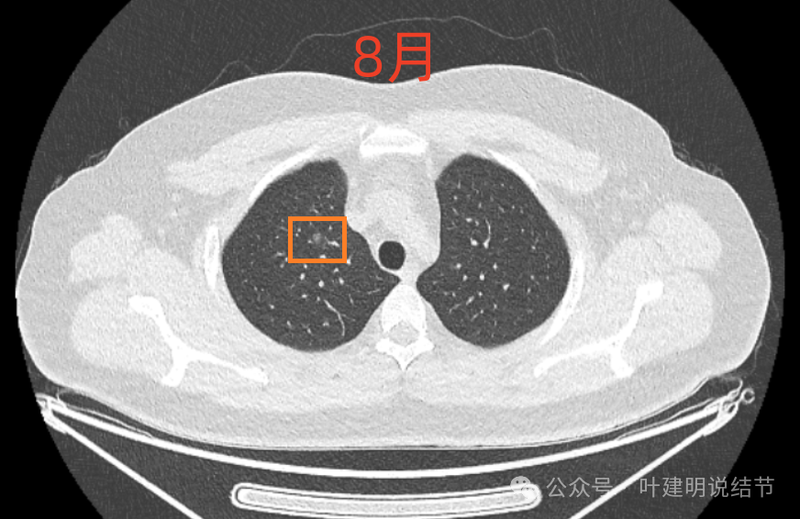

2024年8月5日年度体检薄层CT显示多发结节,2024.11.14复查发现其中一个混合磨玻璃结节新见实性密度影,未诉明显不适,为进一步治疗,特来问诊。

右肺尖磨玻璃结节,整体轮廓与边界清,有微小血管进入与穿行,但肿瘤本向说不上实性密度。

8月时似乎略模糊点,但显著的变化显然仍是说不上的。风险并不能算高,当然东西是肿瘤范畴的,原位癌或不典型增生均可能。

这样的对比,似乎略有变化,又似乎说不上明显变化。本身扫描条件也可能不同。所以我常强调,不要在意过于细微的变化,因为这不影响临床决策。而影响到决策的变化一眼就看出来了。有些同道呀,喜欢拿放大镜看,然后告诉患者有进展,很危险,得尽快手术!只能呵呵了。下面是不同指南与共识对于随访的建议,大家可以自己看。

现在的人工智能辅助诊断系统太过敏感,非常微小的结节都给你找出来,但是对于临床来说并没有多大意义。当结节才几个毫米的时候,既没有办法明确到底是什么,也没有必要明确到底是什么,按照中华医学会肺癌诊疗指南,8毫米以下纯磨玻璃结节或5毫米以下实性结节(包括混合密度结节实性成分不足5毫米)也就是年度复查就可以。所以其实并不一定要在意到底有多少处结节,或者要考虑是什么。主要就关注最主要的病灶,如果主病灶仍没有风险可以年度体检复查,那就可以随访,不能也不必有过大的思想顾虑。我看了你的CT,目前这些结节均风险小,其中右侧桔色框起来的是所谓主病灶,仍是纯磨密度,又还小,考虑不典型增生可能性较大;左下桔色的也是磨玻璃密度,但轮廓不如右上这处清楚,若确实肿瘤范畴,也是原位癌或不典型增生可能性大,但也有少许慢性炎伴肺泡上皮增生或纤维增生的可能性;中叶绿色的密度过高,更符合良性些;右下黄色的过小,11月份的像磨玻璃密度,边界较清,但对比8月时的,此灶不太明显,当然本身过小,也可能没有扫到最明显层面,不过总归风险小,能观察随访(左下的也8月时更显淡和不明显点)。总体上,这几处病灶都是风险还低,可以继续半年到一年复查随访,真若有明显进展并具有一定的风险再来干预处理不影响预后。本身年纪轻,又是多发结节,目前的病灶又都风险低,可以过于积极赶紧处理。意见供参考!